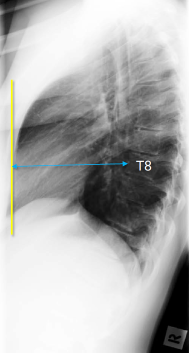

Q what is the name of this measurement? and what is the average + range?

A: Thoracic Cage Dimension

sagittal distance between the posterior aspect of the sternum and the anterior surface of the T8 body.

The average is 14 cm for males (range 11-18 cm) and 12 cm for females (range 9-15 cm).